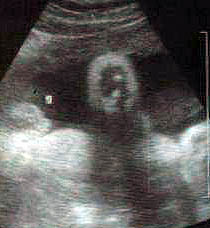

وألحين صور 3D ثلاثية الابعاد

أولا : البنت الاسبوع ال35